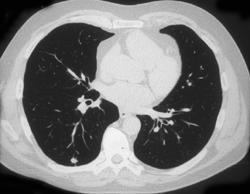

Thoracic Duct With Contrast